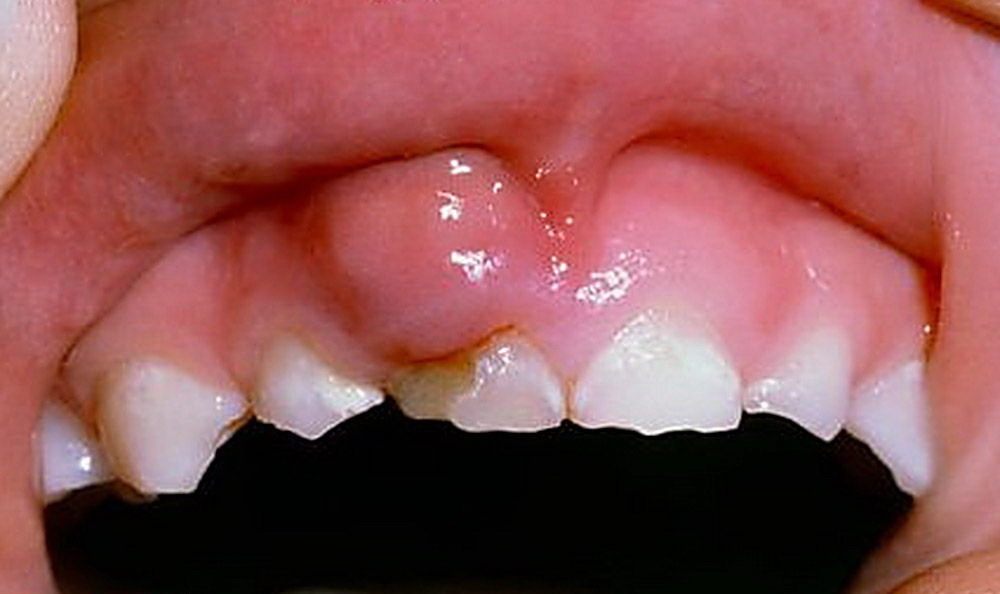

При этой форме периодически появляется ощущение тяжести и распирания или боль слабой интенсивности. Очень часто в проекции корня формируется свищевой ход, через который наружу отходит гной и грануляции. После такого спонтанного опорожнения очага симптомы стихают.

Объективно отмечается гиперемия (покраснеие) десны в зоне причинного зуба. Вертикальная и горизонтальная перкуссия вызывает слабоположительную реакцию. Регионарные лифоузлы увеличены в размерах и болезненны при пальпации. В качестве одного из диагностических критериев рассматривается симптом вазопареза – при давлении на отечную десну тупым предметом (например – обратной стороной пинцета или ручкой зонда) формируется ямка, исчезающая не сразу.